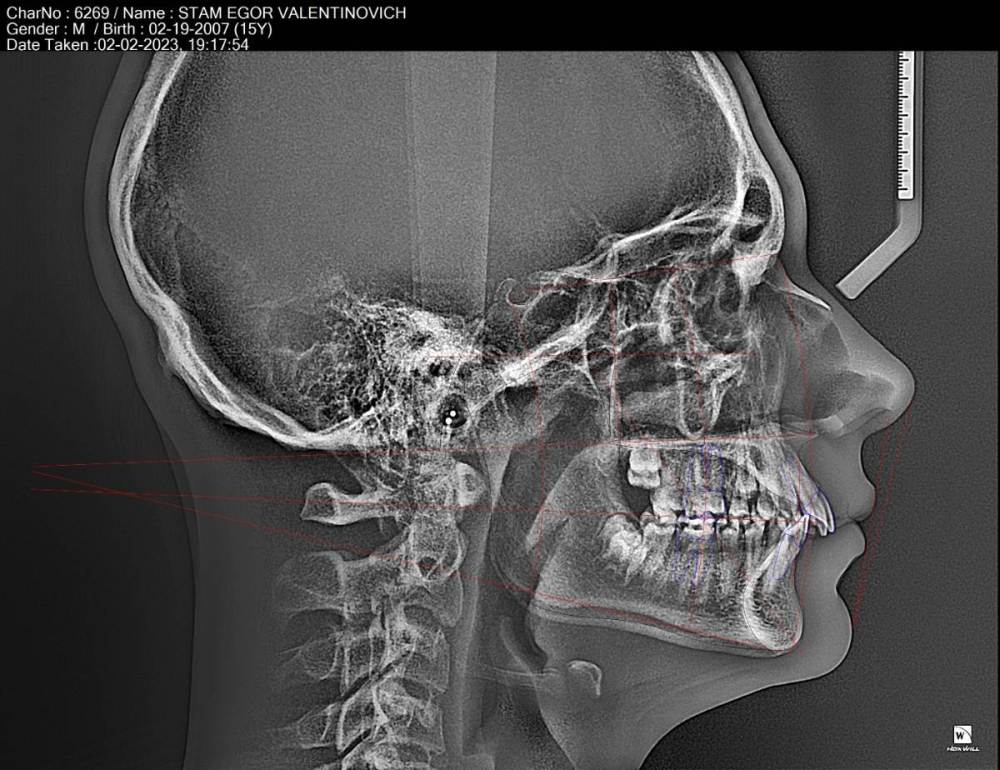

Доброго дня ! у ребенка неправильный прикус ,каждый врач Калининграда советует разные методы ,взываю о  помощи и буду благодарна за любую информацию.

Стам Егор Валентинович ТРГ трассированная.jpg

Стам Егор Валентинович заключение.pdf Стам Егор Валентинович расчёт Пикассо.pdf